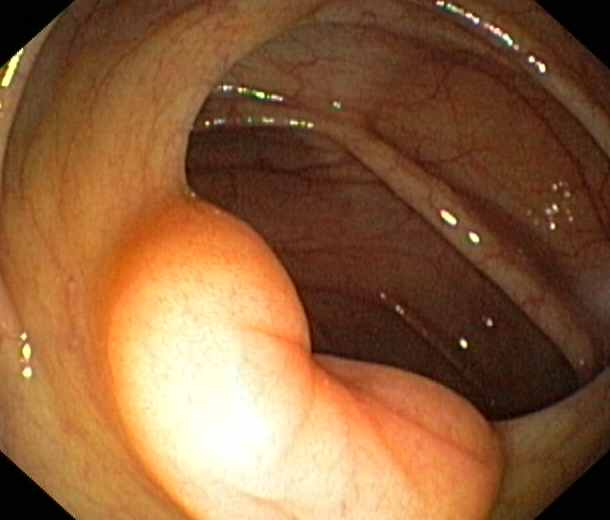

Ileocaecal valve